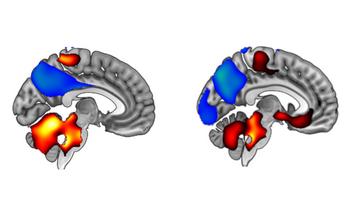

Podjetji Eisai in Biogen sta že septembra sporočili, da je zdravilo zmanjšalo stopnjo kognitivnega upada na lestvici klinične demence (CDR-SB) za 27 odstotkov v primerjavi s placebom.

V torek so objavili poročilo 18-mesečne študije, v kateri je sodelovalo 1800 bolnikov v zgodnjem stadiju Alzheimerjeve bolezni.

Polni podatki so pokazali, da nekateri bolniki z genetskim tveganjem za razvoj bolezni niso imeli koristi od lecanemaba na podlagi meritve CDR-SB. Vendar pa se je pokazalo izboljšanje pri sekundarnih ciljih preizkusa, vključno z drugimi merili kognicije in vsakodnevnega življenja.

Podjetje Eisai je ob tem sporočilo, da so se pri 68 odstotkih udeležencev možgani očistili beljakovine amiloid. Zdravilo je tudi znižalo raven beljakovine tau, ki tvori nevarne skupke v možganskih celicah.

Študija je sicer pokazala tudi na nevarne stranske učinke zdravila, ki je bilo povezano z nevarno vrsto otekanja možganov pri 13 odstotkih bolnikov.